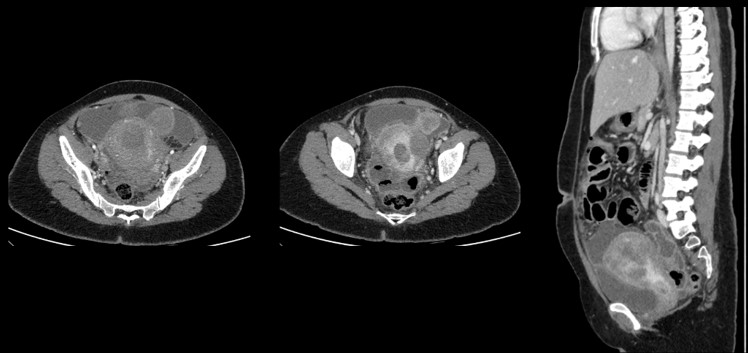

• D. Bulky uterus with a hypodense submucosal lesion protruding into the endometrial cavity from the fundus showing heterogeneous enhancement - infected vs infarcted fibroid. Abnormally enhancing endometrial lining with hypodense content within the endometrial cavity - possible endometritis with pyometra. Pelvic peritonitis with residual trace fluid in the pelvis. Interval resolution of pneumoperitoneum. Abdominal drains in situ.

• E. Bulky uterus with a hypodense submucosal lesion protruding into the endometrial cavity from the fundus showing heterogeneous enhancement - infected vs infarcted fibroid. Abnormally enhancing endometrial lining with hypodense content within the endometrial cavity - possible endometritis with pyometra. Left sided pyosalpinx.

• Bulky uterus with a hypodense submucosal lesion protruding into the endometrial cavity from the fundus showing heterogeneous enhancement - infected vs infarcted fibroid.

• Abnormally enhancing endometrial lining with hypodense content within the endometrial cavity - possible endometritis with pyometra

• Left sided hydro/pyosalpinx.